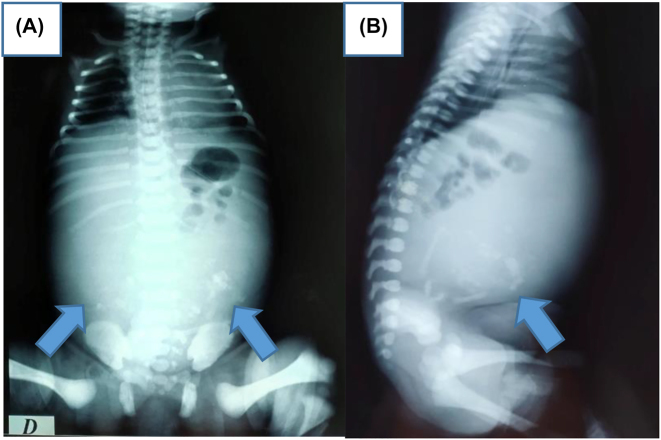

Objectives: Fetus-in-fetu is a rare congenital anomaly that occur secondary to abnormal embryogenesis in a diamniotic monochorionic pregnancy. Its diagnosis can be accurately made by imaging ultrasonography, radiography, computed tomography, or magnetic resonance imaging. Differential diagnosis is an important issue because FIF, teratoma and cystic meconium peritonitis are very different in terms of their respective disease courses.

Case presentation: This is an interesting rare case of a 22-year-old pregnancy woman, presented for a routine antenatal ultrasound. The diagnosis of a fetus-in-fetu was suspected, complete surgical excision of the lesion was performed and the diagnosis was histopathologically confirmed.

Conclusions: We describe also the common characteristic of FIF as revealed by prenatal and postnatal US, postnatal MRI, and the operative findings.